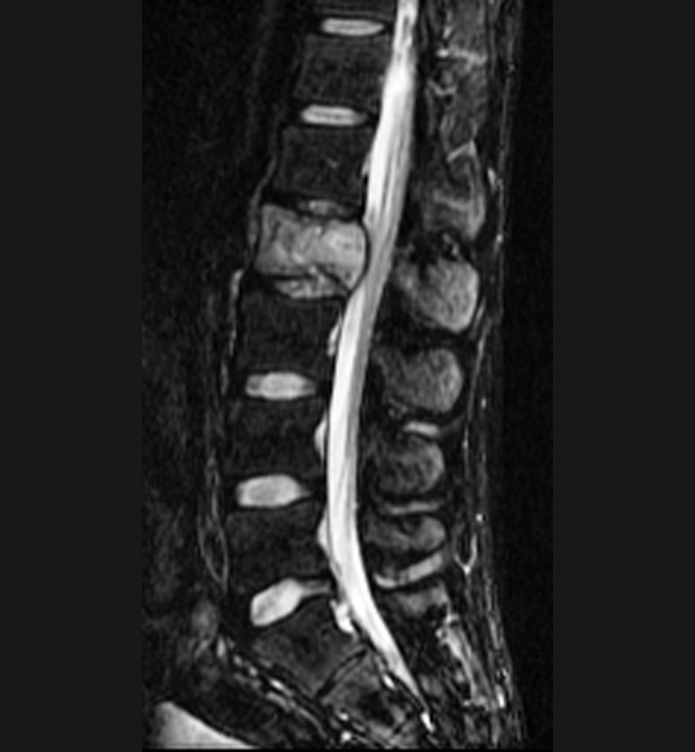

Basit Omurga ve Omurilik Anatomisi Omurga, 33 adet omur kemiğinden oluşur. Bu kemiklerin 7 tanesi boyun omuru, 12 tanesi sırt omuru, 5 tanesi bel omurudur. Beş tanesi birleşmiş olarak sakrum denilen kemiği ve 4 tanesi yine birleşmiş olarak koksiks denilen kuyruk sokumu kemiğini oluşturur. Omurganın görevi omuriliği korumak ve gövdeyi dik pozisyonda tutmak için destek […]